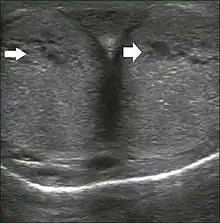

Ultrasonography

Penile ultrasonography with doppler can be used to examine the erect penis. Most cases of ED of organic causes are related to changes in blood flow in the corpora cavernosa, represented by occlusive artery disease (in which less blood is allowed to enter the penis), most often of atherosclerotic origin, or due to failure of the veno-occlusive mechanism (in which too much blood circulates back out of the penis). Before the Doppler sonogram, the penis should be examined in B mode, in order to identify possible tumors, fibrotic plaques, calcifications, or hematomas, and to evaluate the appearance of the cavernous arteries, which can be tortuous or atheromatous.[39]

Erection can be induced by injecting 10–20 µg of prostaglandin E1, with evaluations of the arterial flow every five minutes for 25–30 min (see image). The use of prostaglandin E1 is contraindicated in patients with predisposition to priapism (e.g., those with sickle cell anemia), anatomical deformity of the penis, or penile implants. Phentolamine (2 mg) is often added. Visual and tactile stimulation produces better results. Some authors recommend the use of sildenafil by mouth to replace the injectable drugs in cases of contraindications, although the efficacy of such medication is controversial.[39]

Before the injection of the chosen drug, the flow pattern is monophasic, with low systolic velocities and an absence of diastolic flow. After injection, systolic and diastolic peak velocities should increase, decreasing progressively with vein occlusion and becoming negative when the penis becomes rigid (see image below). The reference values vary across studies, ranging from > 25 cm/s to > 35 cm/s. Values above 35 cm/s indicate the absence of arterial disease, values below 25 cm/s indicate arterial insufficiency, and values of 25–35 cm/s are indeterminate because they are less specific (see image below). The data obtained should be correlated with the degree of erection observed. If the peak systolic velocities are normal, the final diastolic velocities should be evaluated, those above 5 cm/s being associated with venogenic ED.[39]